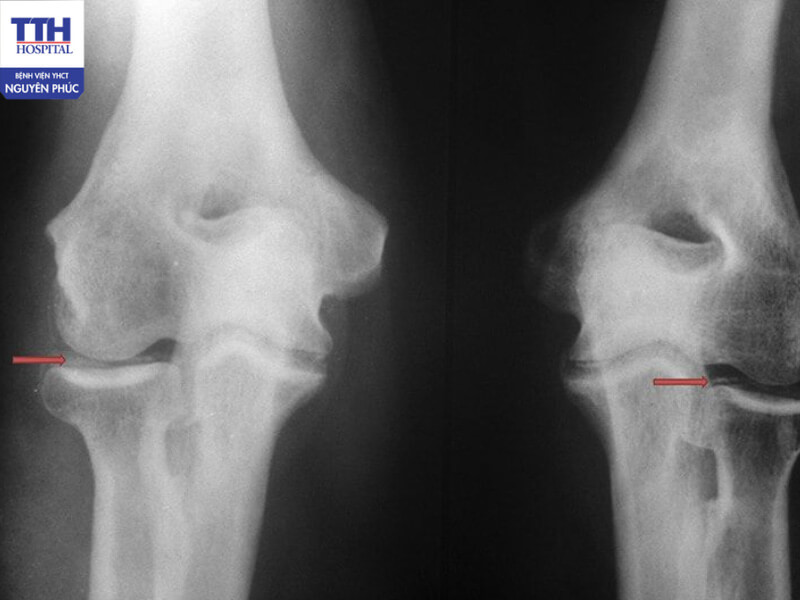

Thoái hóa khớp là quá trình tổn thương và mất dần cấu trúc của sụn khớp theo thời gian. Tình trạng này có thể xảy ra ở bất kỳ khớp nào trên cơ thể, phổ biến nhất là khớp gối, khớp háng, cột sống và khớp ngón tay.

Người mắc thoái hóa khớp thường gặp các biểu hiện như đau âm ỉ tại khớp, cứng khớp vào buổi sáng, khó vận động hoặc đi lại, kèm theo hiện tượng khớp phát ra tiếng kêu khi di chuyển.

Thoái hóa khớp là quá trình tổn thương và mất dần cấu trúc của sụn khớp theo thời gian